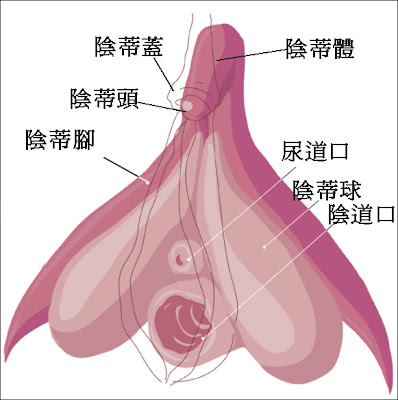

但现在我们已经了解,阴蒂其实包含了很多个部位

过去所说的阴蒂现在被称为阴蒂头

只是整个阴蒂露在体外的一小部分

而其他在体内的还有阴蒂体、阴蒂脚、阴蒂球、尿道海绵体(G点)......等等

这次 Emily 就跟大家介绍一下新定义:

阴蒂到底是怎么一回事?

阴蒂头: 阴蒂头有 6~8千条的神经末梢

所以为了保护这么敏感的地方,在平常的时候阴蒂头会有阴蒂盖保护

当女性感到性奋时阴蒂头才会露出接受更多的刺激

阴蒂体:跟阴蒂头连结在一起,位于身体内、但有的的女性会有部分外露

让阴蒂头整个看起来就像小小的阴茎一样

而事实上阴蒂体确实也如阴茎一样是由海绵体所构成 当妳感到兴奋时,它会充血并像阴茎一样坚硬的勃起

只不这些都发生在体内没办法看清楚

不过你下次可以用手摸摸阴蒂头周围的皮肤仔细感觉一下 应该可以感觉它的存在 (男性要观察请温柔一些、要是被踢下床概不负责)

阴蒂脚:齁~齁~,难怪我不是每次都有高潮

阴蒂脚连着阴蒂体向下延伸,并分裂成两个圆柱状物向两旁伸出

将阴蒂体固定在耻骨位置上,长度约有 5~9公分,在兴奋时它也会充血勃起。

阴蒂球:一样是由海棉体所组成

围绕于尿道上方然后分裂成两个小球分列于阴道两侧